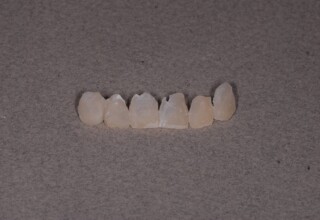

Οι όψεις πορσελάνης είναι ο καλύτερος τρόπος αντιμετώπισης αισθητικών προβλημάτων στην πρόσθια περιοχή του στόματος. Συνδυάζουν συντηρητική αφαίρεση οδοντικής ουσίας και πολύ υψηλή αισθητική απόδοση. Στο παρακάτω εκτεταμένο περιστατικό υπήρχαν: παλαιά σφραγίσματα, δυσχρωμίες, κακό σχήμα και μήκος δοντιών, κακή αναλογία δοντιών-ούλων. Έγινε προσεκτικός εργαστηριακός σχεδιασμός σε εκμαγεία απ’όπου προέκυψαν προσωρινές όψεις που τοποθετήθηκαν στο στόμα για δοκιμή και διορθώσεις. Όταν οριστικοποιήθηκαν οι μετατροπές, οι προσωρινές χρησιμοποιήθηκαν σαν οδηγός για τις μόνιμες. Οι πέντε μόνιμες όψεις πορσελάνης που κατασκευάστηκαν για τα πέντε πρόσθια δόντια της άνω απεκατέστησαν σχεδόν άψογα την αισθητική εμφάνιση της ασθενούς.

Εκτεταμένη αποκατάσταση με στεφάνες(θήκες) σχεδόν σε όλα τα δόντια λόγω εκτεταμένων αποτριβών, παλαιών αποκαταστάσεων, οπισθίων απονευρώσεων και αισθητικών προβλημάτων. Ο ασθενής(60 ετών) παρουσίαζε έντονο βρυγμό (τρίξιμο δοντιών) που δεν είχε αντιμετωπίσει ποτέ, με αποτέλεσμα μεγάλες αποτριβές που απειλούσαν την ακεραιότητα των οπισθίων δοντιών. Οι ανασυστάσεις(σφραγίσματα) των δοντιών έγιναν κυρίως με συγκολλούμενα ρητινώδη υλικά και τρεις χυτούς άξονες ψευδοκολοβώματα. Τοποθετήθηκαν προσωρινές στεφάνες όπου εκτιμήθηκε το επιθυμητό μέγεθος, το σχήμα και η θέση των δοντιών πριν κατασκευαστούν οι τελικές μόνιμες στεφάνες.

Χρησιμοποιήθηκαν παλαιές χαμογελαστές φωτογραφίες της ασθενούς γιατί είχε χαθεί τελείως το φυσικό σχήμα των δοντιών εξαιτίας των πολλαπλών προσθετικών προσπαθειών που είχαν γίνει στο παρελθόν. Μεταφέρθηκε στην προσωρινή γέφυρα η σχέση των φυσικών δοντιών μεταξύ τους άλλα και με τα χείλη. Δοκιμάστηκε η φώνηση και η μάσηση με δυο διαφορετικές προσωρινές άνω γέφυρες και εκτιμήθηκε η αισθητική απόδοση τους. Αφού επιτεύχθηκαν σε βαθμό ικανοποιητικό η φώνηση και η αισθητική εμφάνιση της οδοντοφυΐας, η προσωρινή αποκατάσταση χρησιμοποιήθηκε ως οδηγός για την τελική.